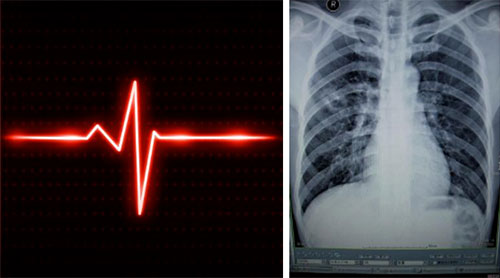

心电图和胸片能比较迅速地完成,可以排除一些危及生命的问题,如急性心肌梗死和气胸、肺炎等。